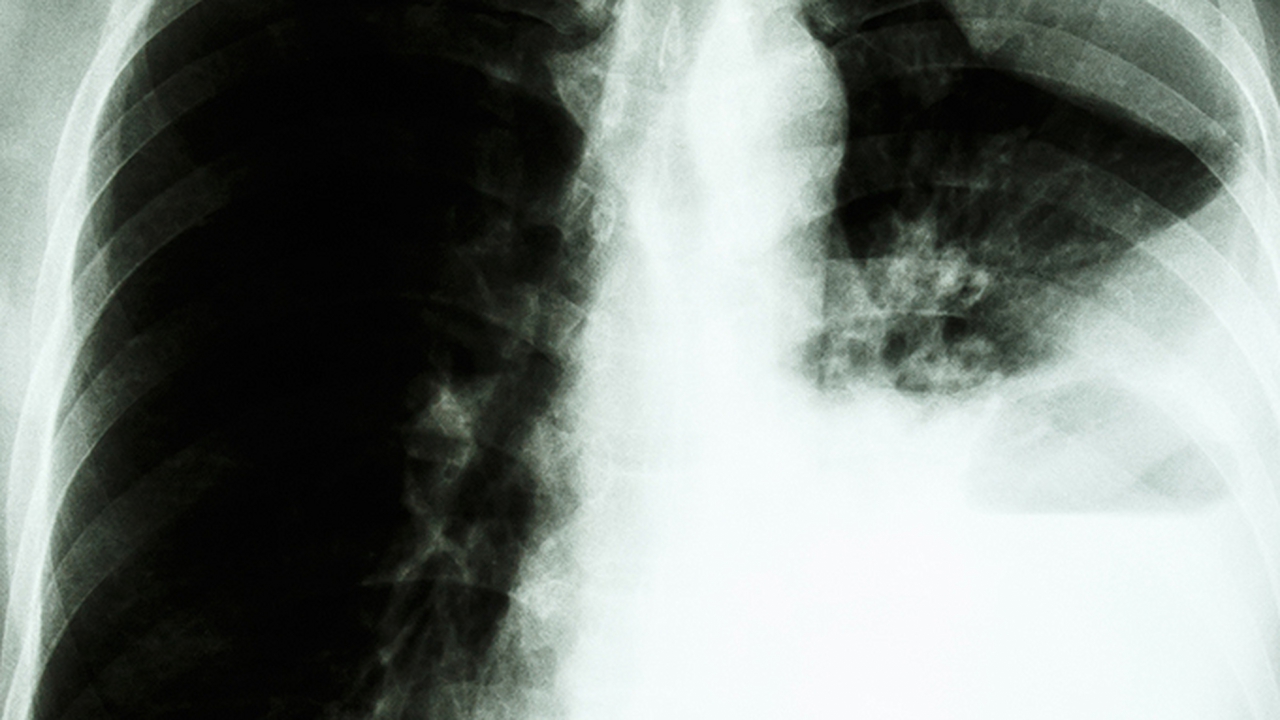

肺癌的发病原因复杂多样,长期吸烟、空气污染、职业暴露、遗传因素等均可能增加患病风险。中医认为肺癌与正气不足、痰瘀互结有关,治疗上注重扶正祛邪、调理整体机能。